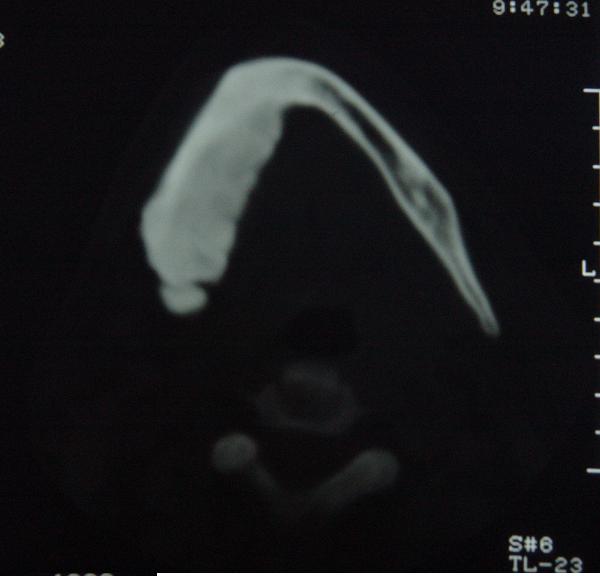

标题: CT12465:下颌骨肿瘤,请会诊 [打印本页]

标题: CT12465:下颌骨肿瘤,请会诊

发现下颌骨肿瘤近30年.逐渐增大.

考虑右侧下颌骨水平部及升部骨纤维异常增殖症可能性大。

考虑右侧下颌骨骨化性纤维瘤。